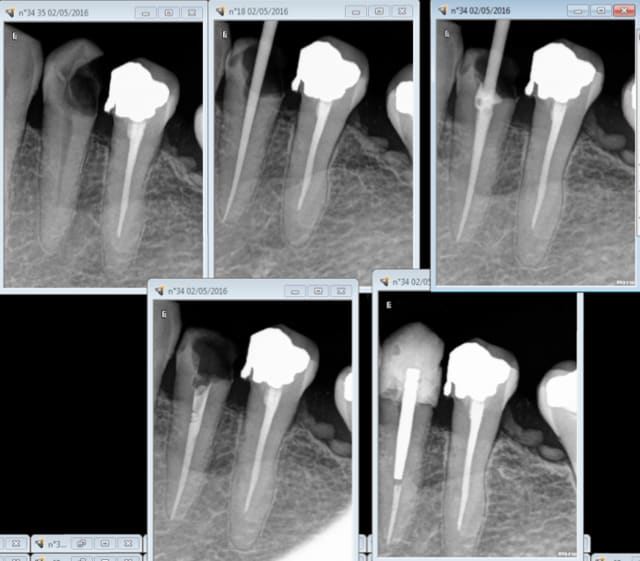

Endo, taille, empreinte, provisoire : 40 mn. Durée de RDV : 1H donc 20 mn pour se détendre et ré attaquer de plus belle le patient suivant. -) -)

J'ai merdé quelque part : devinez ou ? -)

30 mn de plus pour RTE taille de la 5. Pfffff taux horaire de merde ! -)))